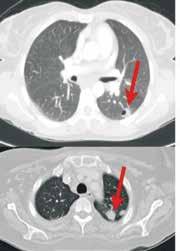

A 34 year old male with history of IVDA (intravenous drug abuse) complains of fever, chills and cough. What is your diagnosis?

Lung Abscess (from septic pulmonary emboli)

Discussion

• Lung abscess is necrosis of lung parenchyma with pus and debris-filled cavities.

• It is caused by direct injury (e.g., aspiration pneumonia) or secondary causes (e.g., tricuspid endocarditis, bacteremia, etc.).

• Suspect with:

o Loss of airway reflexes (e.g., CVA, seizures, alcohol / narcotic abuse, etc.)

o Poor dentition

o Immunosuppression

o IVDA

• Gram positives, negatives and anaerobic bacteria have all been implicated.

• Chest X-ray may suggest diagnosis, but CT scan better identifies abscess, necrotic tissue, empyema, or other pathology (see image above).

• After drawing blood cultures, broad-spectrum antibiotics should be started and narrowed once culture data is available; address underlying cause (e.g., valve replacement for endocarditis).

• Prognosis is generally good with normal immune function and antibiotics, but mortality sharply increases with immunocompromise and treatment delay.